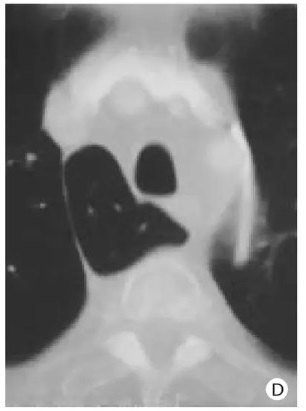

Image radiologique IRM normale du

thorax en coupe coronal ponderee sur T2 . Image de

la plevre est mal de interpreter |

Même cas en coupe IRM axiale

ponderee sur T2 . |